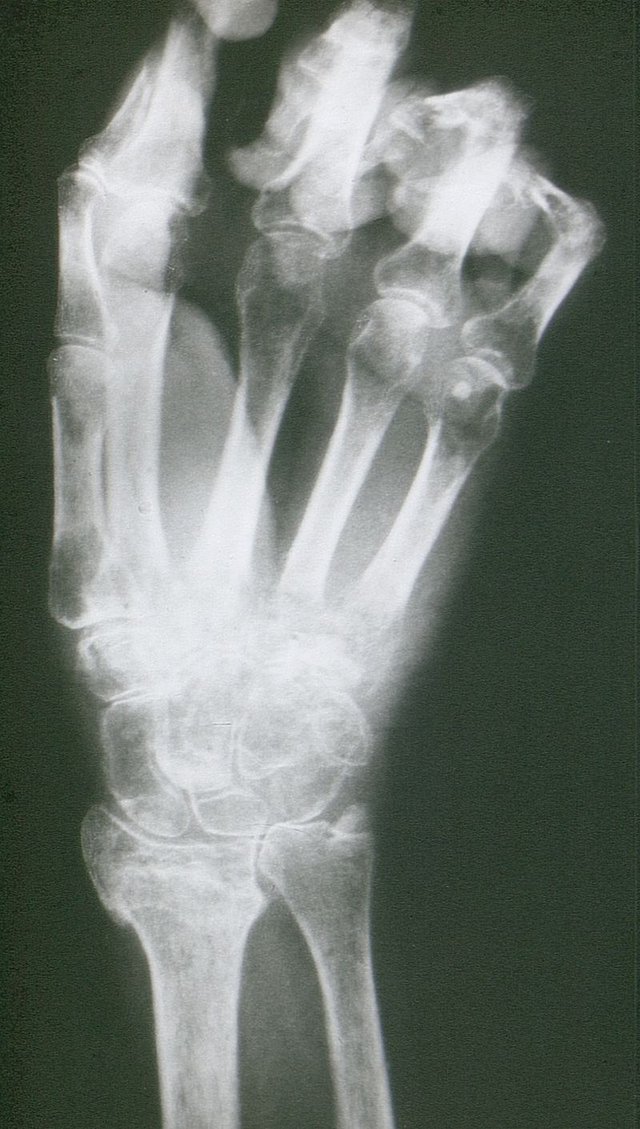

Sudeck-Dystrophie der rechten Hand nach schlecht verheilter distaler Radiusfraktur. © wikipedia.org/Mehlauge (Orthopädische Universitätsklinik Kiel), CC BY-SA 3.0.

• Konventionelle Röntgenaufnahmen im Seitenvergleich (nach 4–8 Wochen kleinfleckige, osteoporotische, gelenknahe Veränderungen – geringe Sensitivität)